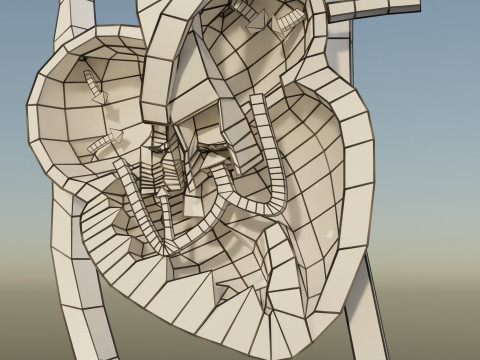

The model meshes include adult circulation versus circulation in Tetralogy of Fallot (TAF), arrow labels and text labels. The blood flow in a patient with Tetralogy of Fallot is outlined in this model. To contrast it to normal blood circulation a separate model of normal circulation is included. The Tetralogy of Fallot (OVER RIDING OF AORTA, PUL STENOSIS, VENTRICULAR SEPTAL DEFECT, RIGHT VENTRICULAR HYPERTROPHY), fossa, ligament teres , venosus, and arteriosus are duly depicted with proper labelling and blood flow directional arrows. Excellent model for teaching, demonstration and knowlegde of human body. The models include both procedural and image textures blend files separately. The texture file include diffuse, roughness and normal png and jpeg based on non overlapping UV maps.

- बहुभुज:285000

- वर्टिसिस:230000